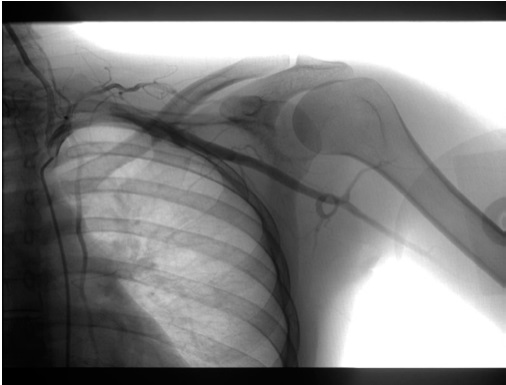

Respecto a las exploraciones complementarias (Figuras 1 y 2), se realizó angio-TAC, donde se informa que visualiza un aneurisma subclavio izquierdo de aproximadamente 2,6 x 1,9 x 1,2 cm, (CC x T x AP), en la porción proximal de la arteria, por detrás de la clavícula. Se indica presencia de arcos costales bilaterales, observando en el lado izquierdo una neoarticulación entre la costilla cervical y la primera costilla que junto a la clavícula pinzan el espacio vascular, como probable causa de la formación aneurismática. No se objetiva correcto llenado de los vasos radiocubitales desde la flexura del codo aproximadamente. Ante estos hallazgos, se realiza arteriografía donde se confirma la presencia de dilatación aneurismática subclavia izquierda, a nivel de zona de compresión costoclavicular, con permeabilidad subclavio-axilar, observando defecto de llenado humeral proximal, con visualización de dos arterias humerales con trombo en ambas, la más medial a pesar del trombo proximal presenta paso distal con relleno radial.